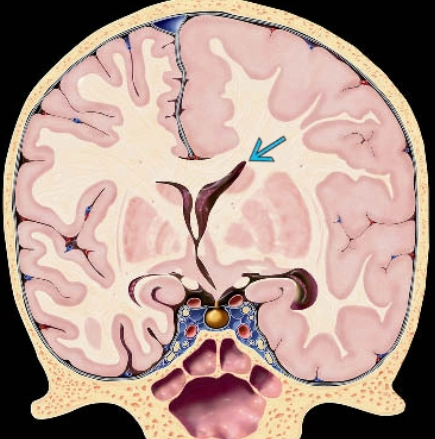

• Bất thường phát triển vỏ não

• Loạn dưỡng cơ bẩm sinh (Các biểu hiện ở hệ thần kinh trung ương) - Congenital muscular dystrophies (Central nervous system manifestations)